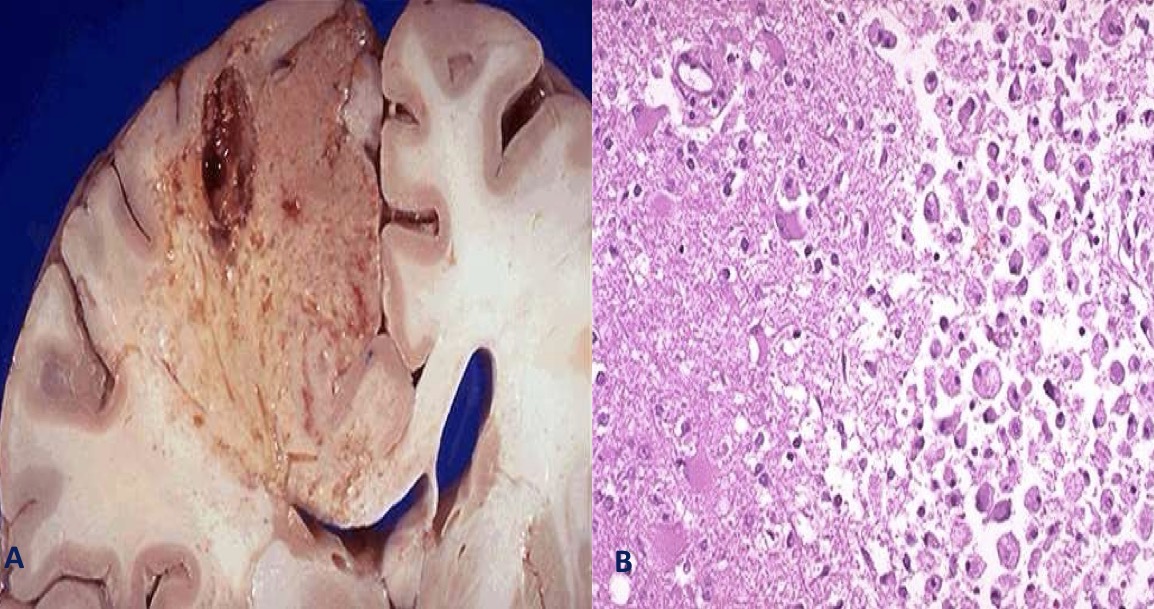

A- identify

B- Describe A&B

A- liquefactive necrosis of brain

B- (A) infarct in the brain showing dissolution of the tissue ,(B) liquefied tissue contains necrotic cell debris and macrophages